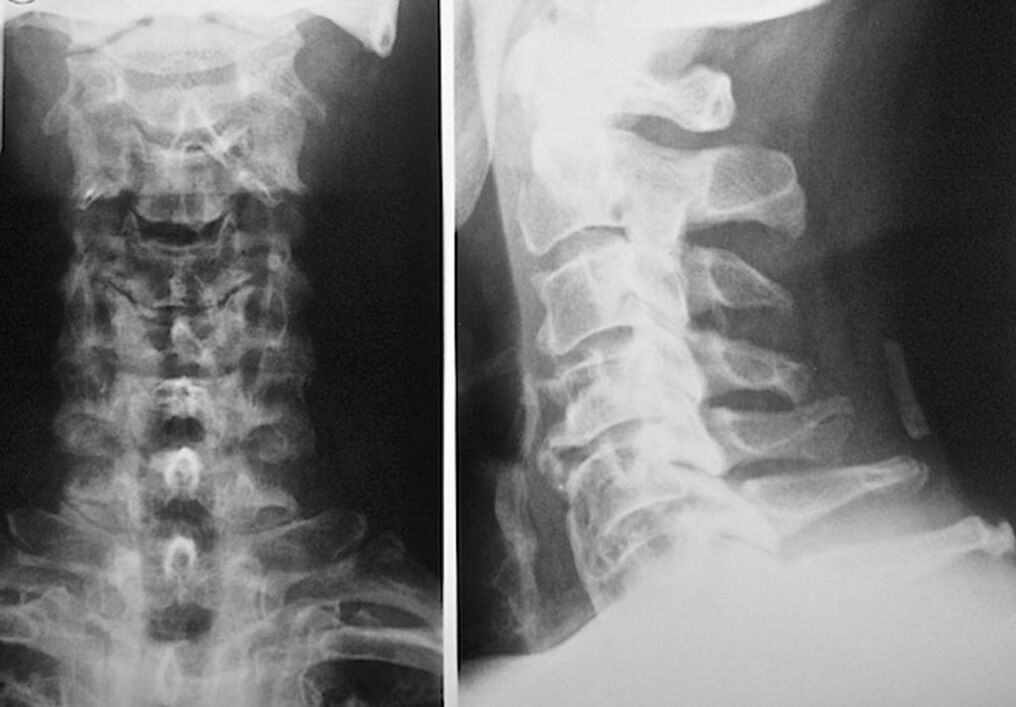

For the diagnosis and accurate assessment of the condition of the intervertebral discs, the following research methods are used:

- X-ray.

- CT.

- Magnetic tomography.

- Ultrasound of the vessels of the neck.

Each of them is completely safe for health and poses no threat of excessive exposure. The diagnosis of osteochondrosis of the cervical vertebrae, the treatment of which will be carried out throughout life, can be made after a simple visual examination. Any orthopedist can easily do this. An exception is the first stage of the disease, when no visible pathology of the cervical region is noticed.